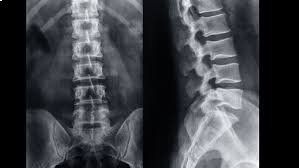

La radiologia convenzionale è l’esame di primo livello per lo studio di molteplici distretti corporei e in particolare dell'apparato respiratorio e scheletrico (cranio, colonna vertebrale, segmenti ossei). Questa metodologia fornisce importanti indicazioni di base su molte patologie, sia traumatiche che degenerative e artrosiche nonché malformative. La radiologia convenzionale si risulta anche di grande efficacia per individuare patologie o problematiche all'apparato urinario e all'addome, da approfondire successivamente con esami diagnostici più accurati e precisi.